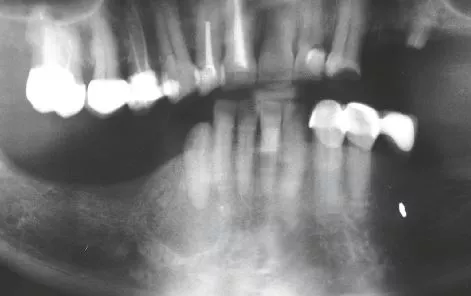

Es stellte sich eine 54-jährige Patientin mit einer extraoralen Fistel regio mentalis rechts in unserer Sprechstunde vor. Allgemeinanamnestisch bestand ein schlecht eingestellter Diabetes mellitus Typ II (HbA1c: 10,9). Klinisch zeigte sich intraoral ein tief zerstörter und auf Gingiva-Niveau frakturierter Zahn 43. Im Orthopantomogramm zeigte sich eine ausgedehnte Osteolyse regio 43. Nach ausführlicher Aufklärung der Patientin erfolgte die operative Entfernung des Zahnes 43 und entsprechende Zystektomie unter peri- und postoperativer antibiotischer Abschirmung mit Amoxicillin 1000 mg 1-1-1. Der Fistelgang nach extraoral wurde kürettiert und zum Teil exzidiert. An den postoperativen Nachkontrollen zeigte sich die Wundheilung regelrecht. Der extraorale Fistelgang heilte vollständig ab (Abb. 3-5).